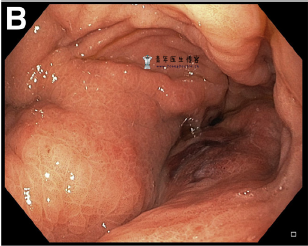

胃镜检查显示胃窦严重扭曲,伴有瘘管(图B,C)。